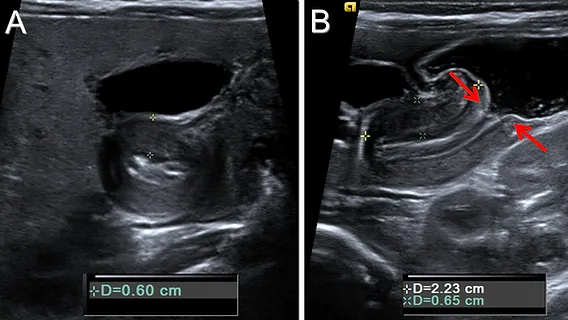

- Abdominal Ultrasound (US): Test of choice.

- Pyloric muscle thickness > 4 mm

- Channel length > 16 mm

- Diagnosis: Abdominal ultrasound is the gold standard, showing a thickened (>4 mm) and elongated (>14 mm) pylorus.